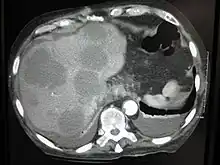

Hematogenous spread

This is typical route of metastasis for sarcomas, but it is also the favored route for certain types of carcinoma, such as renal cell carcinoma originating in the kidney and follicular carcinomas of the thyroid. Because of their thinner walls, veins are more frequently invaded than are arteries, and metastasis tends to follow the pattern of venous flow. That is, hematogenous spread often follows distinct patterns depending on the location of the primary tumor. For example, colorectal cancer spreads primarily through the portal vein to the liver.